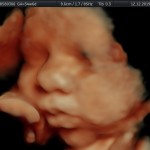

Modalidad de imagen ecográfica que permite evaluar, medir y capturar estructuras fetales superficiales e internas en 3 dimensiones (3D) y también en movimiento y en tiempo real (4D) con programas de realismo aumentado (HD LIVE) e imágenes tomografías fetales (TUI) mejorando significativamente la precisión en las mediciones fetales y la documentaciones de estructuras anatómicas.

Esta tecnología se puede utilizar desde la 6ta a la 40ma semana de embarazo.